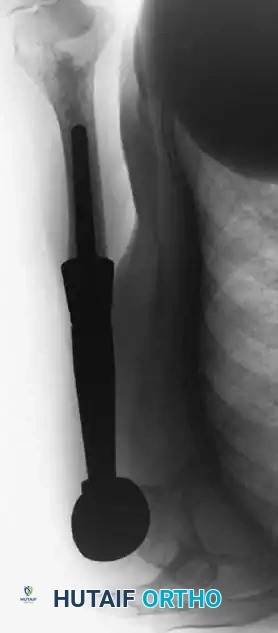

* Endoprosthetics: Modular megaprostheses are commonly used for metaphyseal/articular resections in older adolescents and adults. Expandable prostheses are utilized in skeletally immature patients to accommodate future growth.

Fig. 22-8 A, Anteroposterior view of the right proximal humerus of a 92-year-old woman with dedifferentiated chondrosarcoma shows an aggressive-appearing area (arrows) adjacent to an otherwise typical chondrosarcoma. B, Resected specimen shows these features. C, Typical microscopic appearance of dedifferentiated chondrosarcoma. High-grade spindle cell sarcoma is located adjacent to low-grade chondrosarcoma. D, Anteroposterior radiograph after reconstruction with an endoprosthesis.